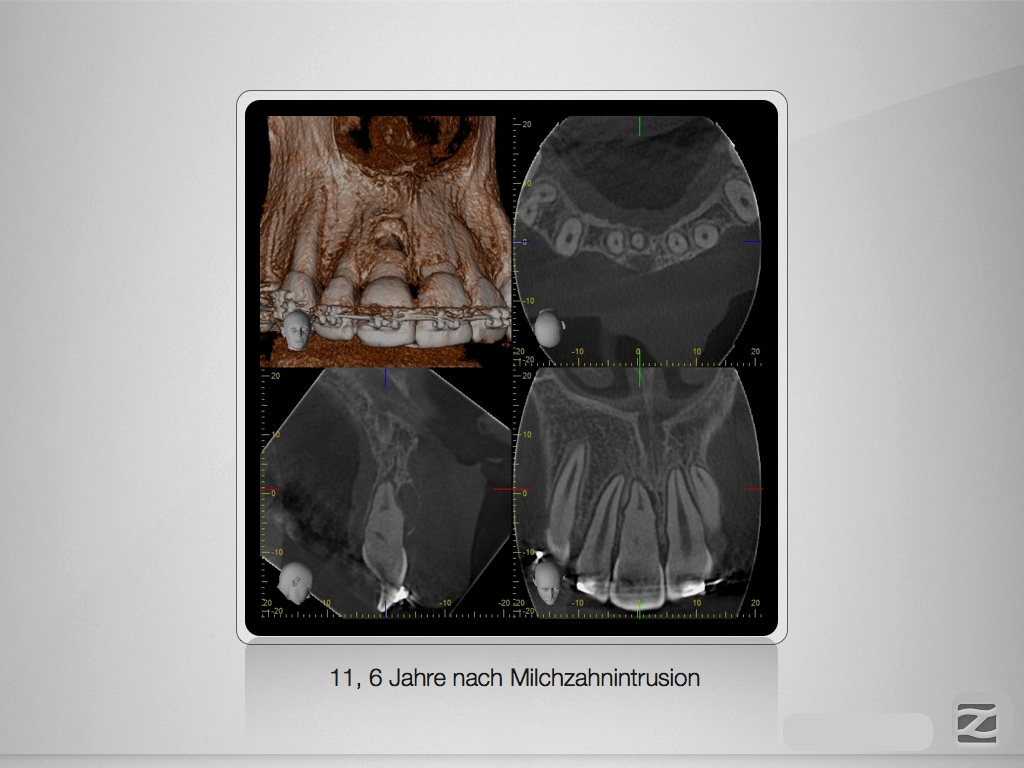

Spätfolge eines Milchzahn-Traumas